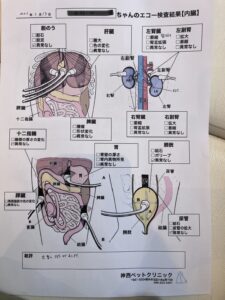

◾️キャットドックによる検査 診察

◾️診断

左の腎臓に石(腎結石)軽度の慢性腎臓病

🍀半年後 血液検査 エコー